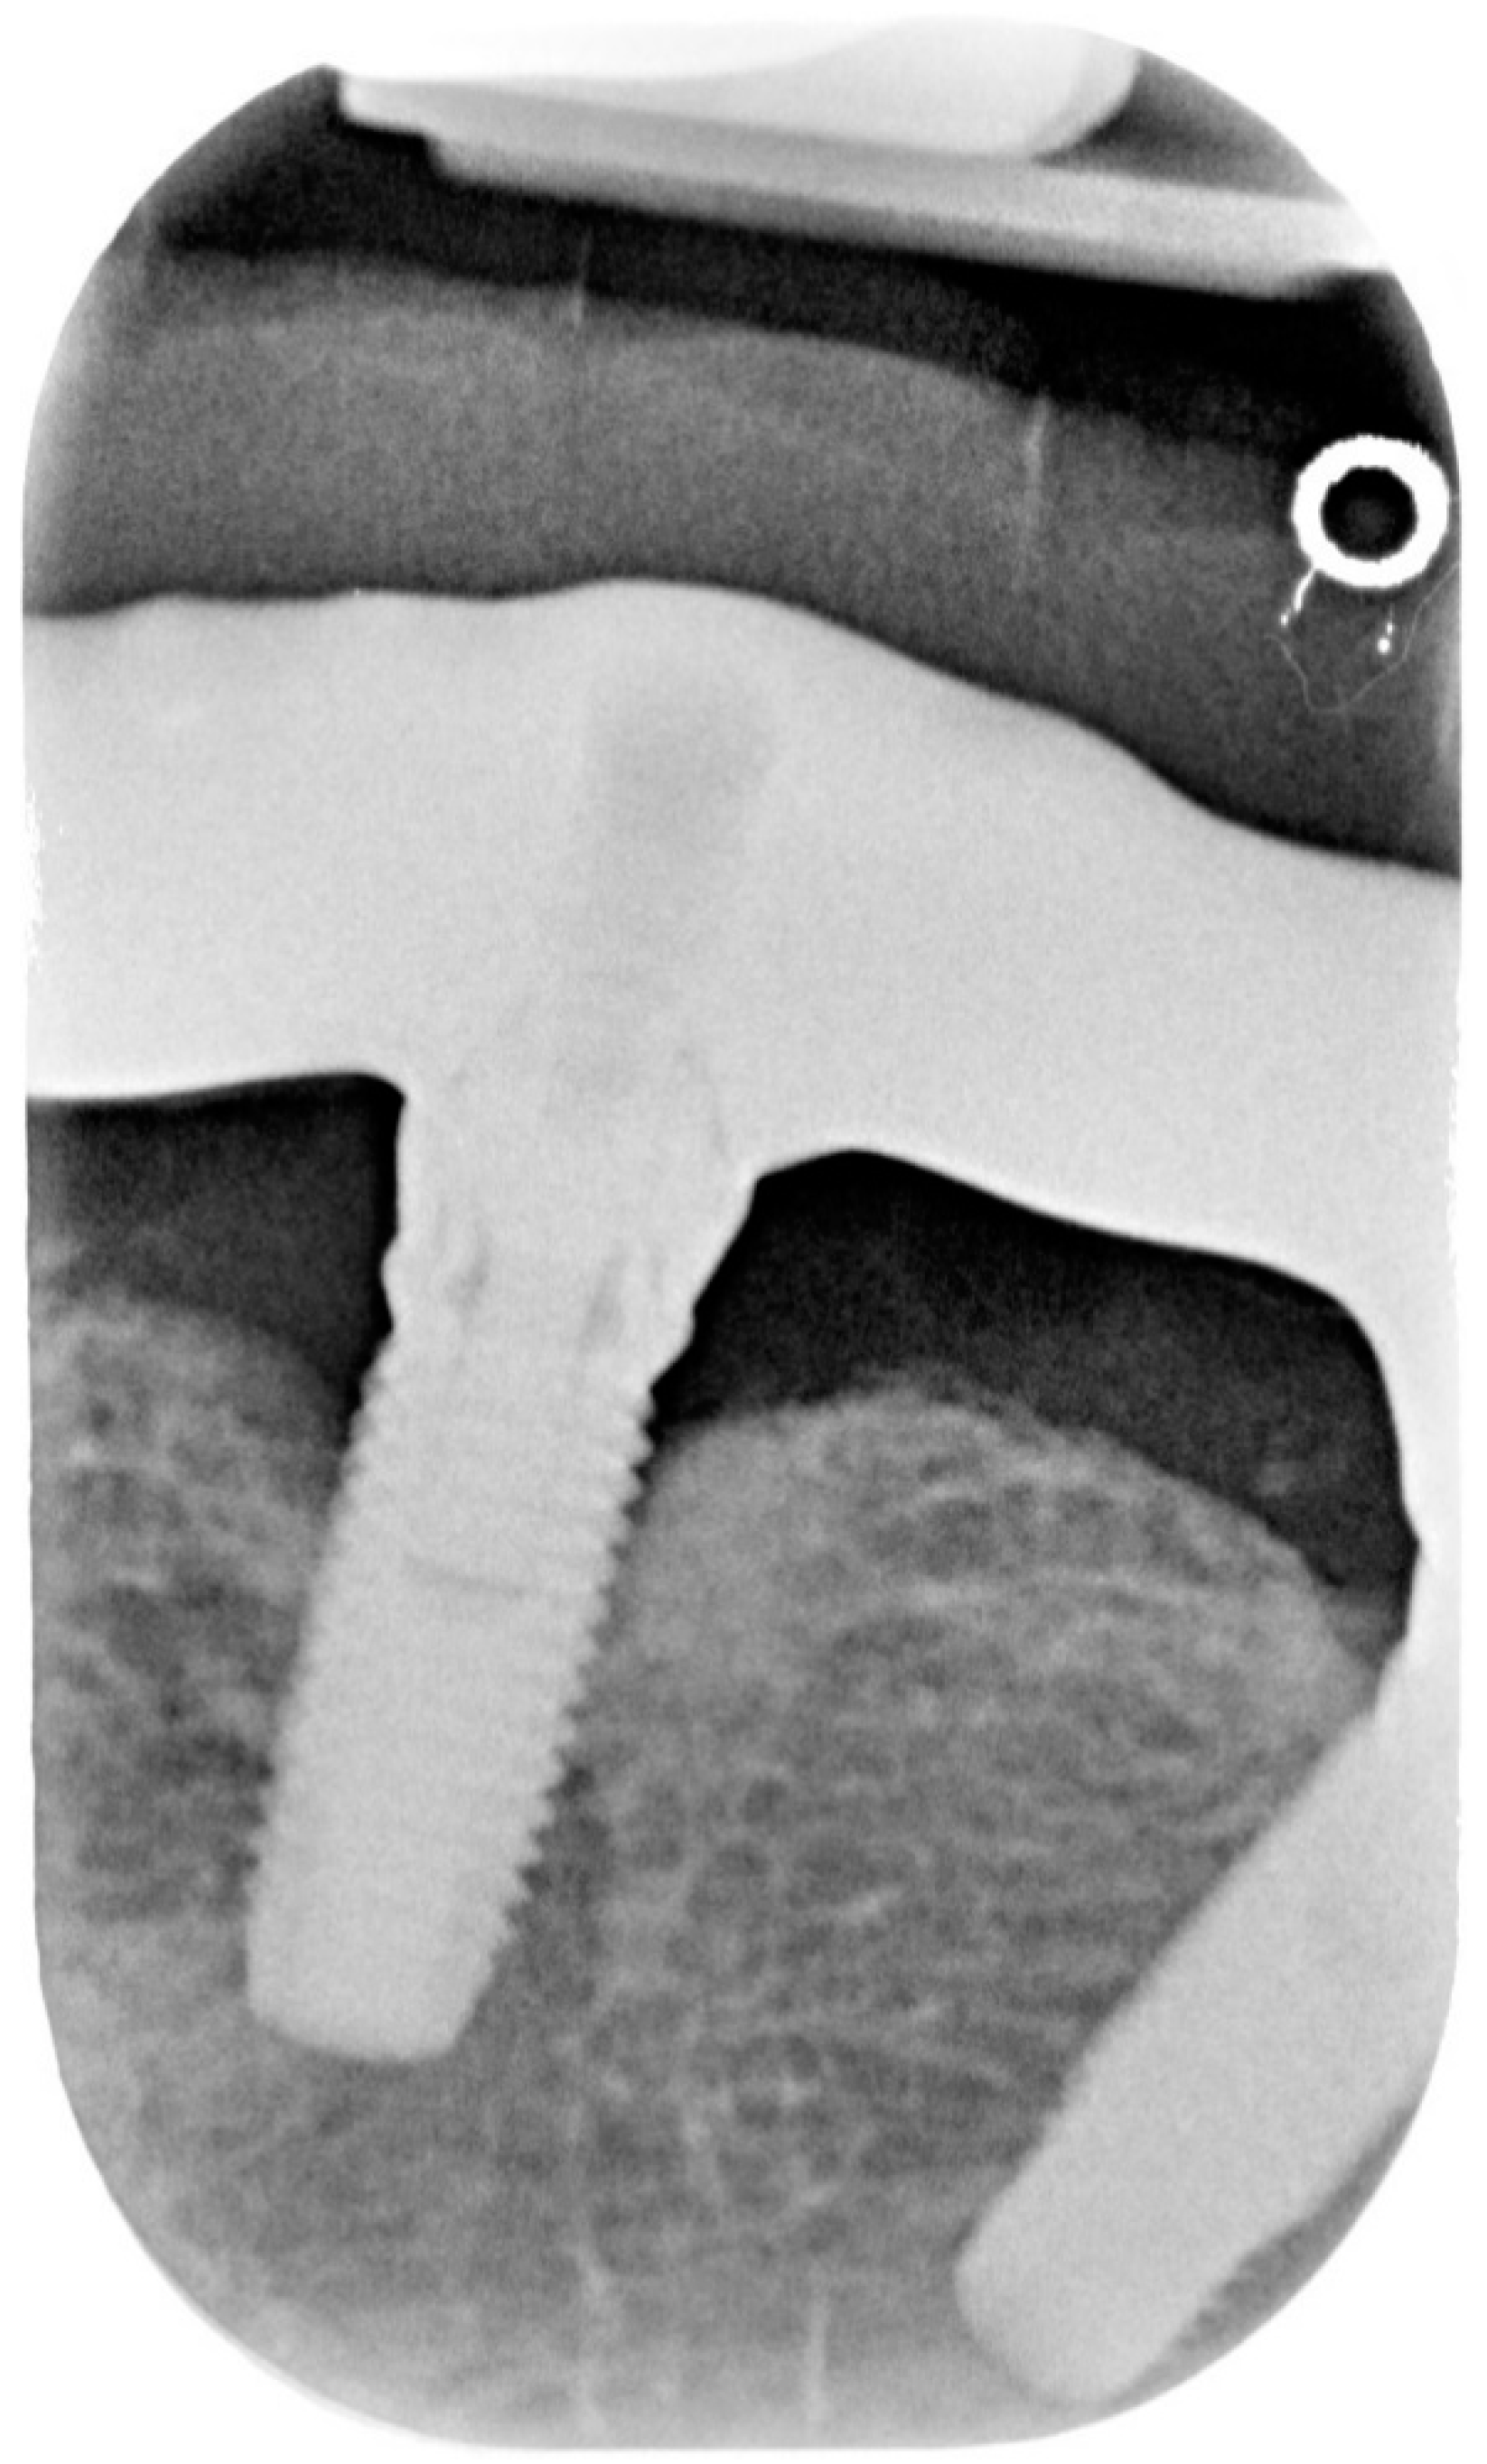

Figure 2.

X-ray of dental implant area before treatment.